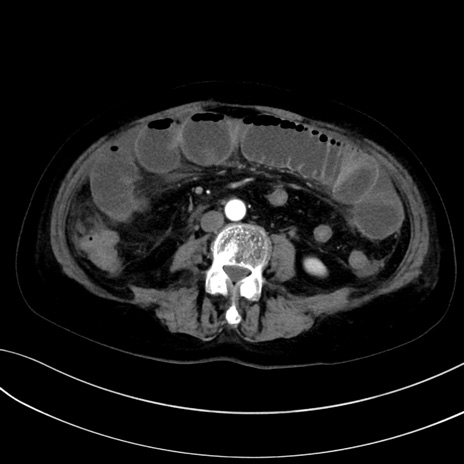

症例13 CT(横断像)1日半後